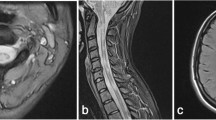

Patients diagnosed with likely antibody-negative NMO in the clinic were all assigned to Group 3 or 4 by the unsupervised algorithm, and these groups differed significantly between each other. Patients from Group 4 had highly destructive disease of the spinal cord and brain as seen in advanced MS, however, they all had a number of red flags for the diagnosis of MS as well. First, all these patients had a history of LETM, considered a hallmark of NMOSD [36] and extremely rare in MS [37]. Four out of six had NMO-like brain lesions, including a lesion adjacent to the 3rd ventricle (patient 3), periaqueductal and hypothalamic lesions (patient 13), oedematous lesion involving the complete thickness of the splenium of corpus callosum (patient 20) and a large hemispheric white matter lesion (patient 21). One patient in this group had a dramatic exacerbation on natalizumab with a formation of ring-enhancing brain lesions (patient 12). These patients are likely to have a disease process that is different from MS, potentially mediated by autoantibodies or other type of inflammation. One of these patients underwent biopsy of the cerebral lesion (Patient 21) which showed chronic inflammation and reactive gliosis without evidence of MS demyelination, granulomatous process, vasculitis or neoplasm. This group may represent a new disease entity.

All patients from Group 3 had a normal brain appearance based on standard imaging and significantly less brain atrophy or white matter disintegrity when compared with Group 4. These patients had predominantly optico-spinal presentation but they had less spinal cord atrophy than Group 4 despite a high proportion of previous LETM in both groups. Two out of five had attacks of both BON and LETM, two had recurrent isolated optic neuritis including at least one attack of simultaneous BON and one had LETM followed several months later by unilateral optic neuritis. Two out of five in this group were left with poor residual visual acuity. This group, as opposed to other groups, did not have any evidence of cortical damage, was the least disabled of all groups (average EDMUS 2.4) and appeared to have a milder form of NMOSD with a high proportion of BON, similar to what is observed in MOGAD [13]. We find it likely that disease process in this group is mediated by yet undiscovered antibodies.

Patients from Groups 1 and 2, despite being referred to NMO clinic, appear to have forms of MS. Brain lesions in these patients, although there were typically only a few of them, were positive for landmark MS features (Group 1). Those without brain lesions (Group 2) had short-segment lesions in the spinal cord but very rarely had NMOSD features, such as LETM (12.5%), BON (0%), poor visual recovery (12.5%) or NMO brain lesions (0%). Of the patients in this group, 50% had unmatched oligoclonal bands in the CSF. This form of spinal MS may turn out to be pathologically distinct and is worth further research.